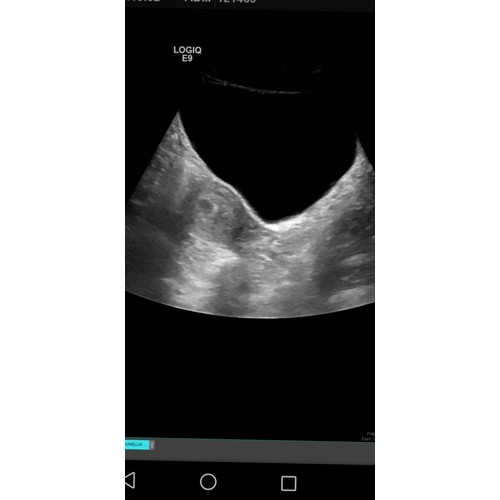

Ik herken jullie onzekerheid en spanning. Heb ik ook gehad. Gelukkig telkens een echo gehad met 5/6 weken. Daarop kon je soms alleen maar een rondje zien, maar wel in de baarmoeder en zodra ik dat wist waren alle zorgen weg!

Dag dames ik had net het zelfste gevoel gisteren naar de huisarts gegaan die mij volledig snapte en heeft een vroege ego gedaan nog geen hartje te zien maar wel dat het in op de juiste plaats zit was al een grote opluchting

Sorry voor de late reactie. Gisteren een eerste echo gehad en het zit op de goede plek!

Al een kloppend hartje te zien en ook te horen. Zei de gynaecoloog alleen dat het hartje nog wat traag klopt en dat ik volgende week terug moet komen en dat het hartje dan echt harder moet zijn gaan kloppen.. volgende waar ik me nu weer zorgen om maak;-) maar we blijven positief!